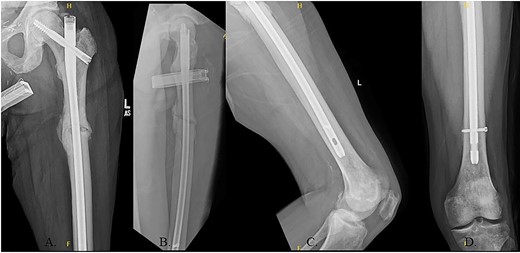

The patient was positioned supine on a fracture table. A guide wire was inserted through a 4-cm surgical incision proximal to the greater trochanter (GT) and was passed through a cannulated awl in a position slightly medial to the tip of the GT on the AP and center on the lateral (Fig. 2B). A (15-mm) entry reamer widened the opening (Fig. 2C). A rigid cannulated reduction rod and forceful malleting allowed the ball-tipped guidewire to cross the close reduced fracture, but too lateral and posterior distally (Fig. 3A and B). The cannulated flexible reamers encountered impassible blastic lesions within the proximal femur (Figs 3C and 5B).

(A) Ball-tipped guidewire slightly lateral position at the knee on the AP XR; (B) ball-tipped guidewire too posterior at the knee on the lateral XR; (C) flexible reamer within the proximal femur abutting blastic lesions.

(A) Canulated cutter tool creating a new path in the proximal femur; (B) rigid canulated reduction rod directing the guidewire across a reduced fracture held with a proximal bone hook and distal ball spike pusher; (C) center positioned ball-tipped guidewire at the knee on the AP XR; (D) center positioned ball-tipped guidewire at the knee on the lateral XR.

The ball-tipped guidewire was extracted, and a sharp cannulated cutter created a novel path in the proximal segment (Fig. 4A). A rigid nonunion reamer (DePuy Synthes©, Raynham, MA) was advanced to widen the canal. Closed reduction was lost and so a lateral incision was made at the level of the fracture and a percutaneous reduction was achieved through use of a proximal bone hook and distal ball spike pusher (Fig. 4B).

The hip was extended, and a ball-tipped guidewire was successfully passed across the fracture site to a center–center positionwithin the canal at the level of the knee (Fig. 4C and D). Sequential 0.5-mm reaming from 9 to 13 mm prepared for an 11 × 400 mm, 125° Gamma3® intertrochanteric rod (Stryker© Kalamazoo, MI), with a 95-mm cephalomedullary screw and ×2 distal lateral to medial interlocking 5.0-mm screws (Fig. 5A–D). Through the course of the procedure, 400 cc of blood loss necessitated two units of packed red blood cells.